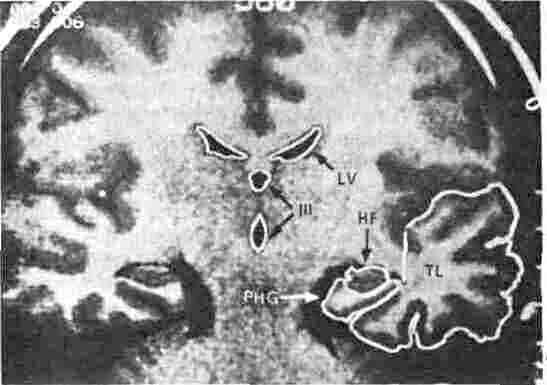

Рис. 5.4. Изображение мозга, полученное с помощью ядерного магнитного резонанса (ЯМР). На рисунке показан фронтальный разрез мозга здорового молодого человека, полученный с помощью неинвазивного метода ЯМР. Темные области в центре (III и IV) — желудочки, HF — гиппокамп, РНО — извилина аммонова рога, TL — височная доля. Штрихи справа расположены через 1 см. У больных с синдромом Корсакова эта область заметно атрофирована, а желудочки увеличены. При некоторых других формах амнезии височная доля повреждена и уменьшена в размерах. (Фото любезно предоставил Лэрри Сквайр; из L.R. Squire, D.G. Amarel, G-A. Press, J. Neurosci., 1990, 10, р. 3106-3117.)

Мозг как физиологическая система на клеточном и химическом уровнях чрезвычайно динамичен. Активные нейроны нуждаются в больших количествах глюкозы и кислорода, и развитая система кровоснабжения мозга в любой момент должна доставлять эти вещества туда, где они всего нужнее. Работа нервных клеток — это электрическая активность, и генерируемый биологическими механизмами ток течет через мозг регулярными и вместе — с тем изменчивыми, как на море, волнами. Кроме того, в силу физической природы электричества протекающий ток создает магнитное поле, перпендикулярное к его направлению. Все эти свойства мозга открывают возможности для получения его изображений. В любой сканирующей системе на поверхности головы размещают по определенной схеме детекторы, причем их может быть тем больше, чем меньше их размеры. В некоторых случаях число различных детекторов достигает 124. Каждый детектор регистрирует возникающие в мозгу сигналы; почти (но не абсолютно) одновременное поступление сигналов на разные детекторы позволяет определять локализацию их источников. Затем компьютерные системы составляют карты «срезов» через мозг в соответствующих координатах, а получаемые черно-белые изображения условно перекодируются компьютером в цветные для облегчения их визуального анализа. Одна из таких карт показана на рис. 5.4.